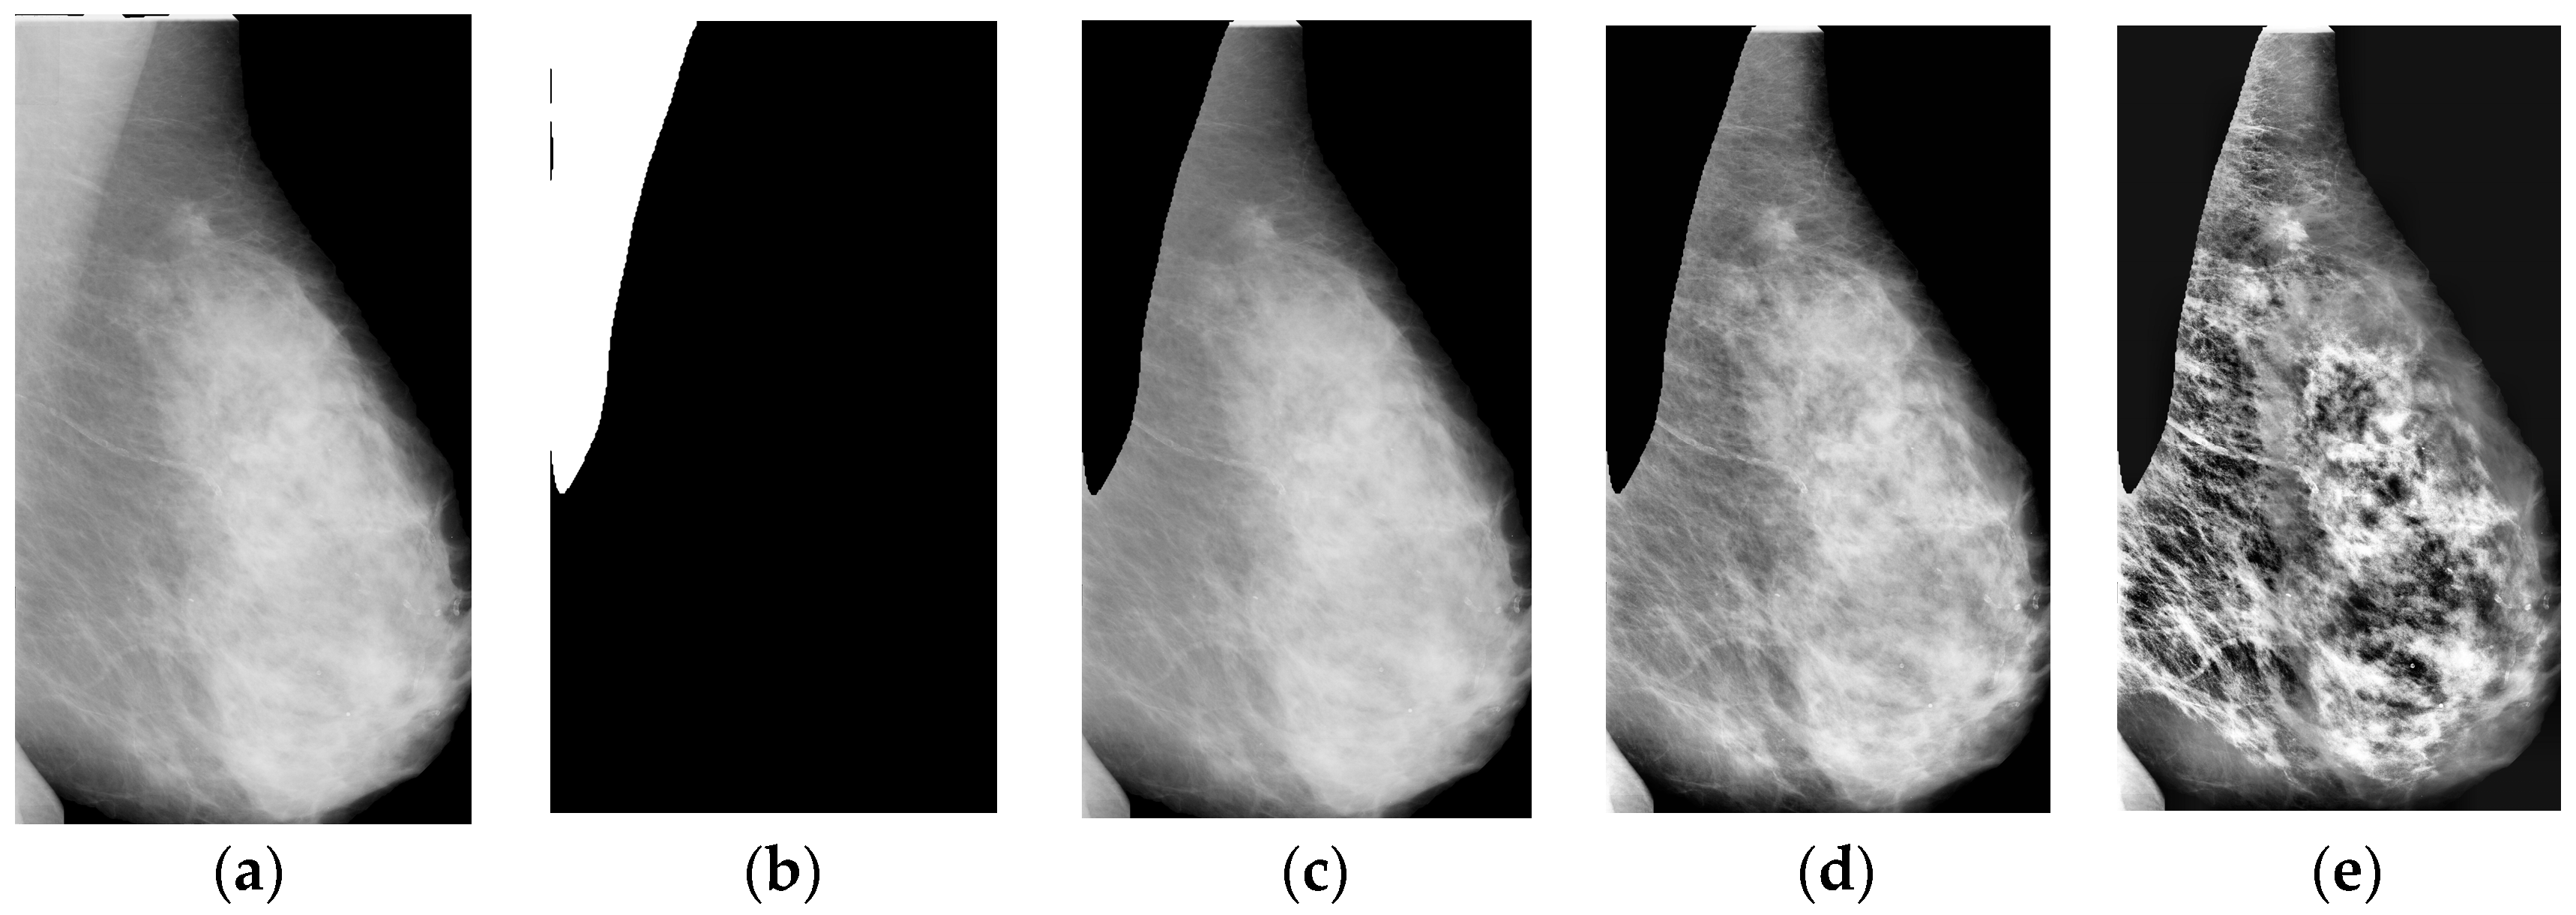

Usually, mammograms have four views, including a left-side craniocaudal (LCC) view, a left mediolateral oblique (LMLO) view, and two counterparts from the right. The main difference between a CC-view mammogram and an MLO-view mammogram is that pectoral muscles are usually shown in MLO-view mammograms, while there is only a little or no pectoral muscle in CC-view mammograms. However, when implementing our framework, we found that the pectoral muscle should be removed as it affects the calculation of GFCF. To this end, we trained an improved version of Deeplabv3+ and completed the breast pectoral muscle removal task as in [23]. One segmentation example can be found in Figure 1. As can be seen from Figure 1b, the pectoral muscle has been successfully segmented and then removed in Figure 1c.

After pectoral-muscle removal, the breast images are then enhanced by contrast-limited adaptive histogram equalization (CLAHE) due to the poor image contrast [24]. The enhanced images can be seen in Figure 1d, where λ denotes the clip limit. Empirically, we set the value of λ to be 0.05 as it provides the best visual image contrast improvement.

Figure 1. Pre-processing examples. (a) Breast-only image. We automatically extract the breast from a mammogram as we are only interested in the breast region. (b) Pectoral segmentation result. (c) Pectoral-muscle-removed breast image. Deeplab3+ model is trained for pectoral muscle segmentation. (d) Breast image enhanced by CLAHE when λ is 0.05. (e) Breast image enhanced by CLAHE when λ is 0.1.